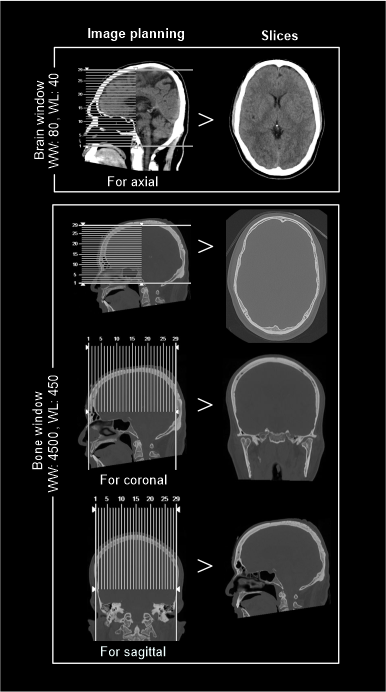

- 5 mm axial, coronal and sagittal images in brain window (WW80, WL40) [7].

- 1-2mm axial, coronal or sagittal images of the skull in bone window (WW3500, WL350) to show fractures, dislocations or bony abnormalities.